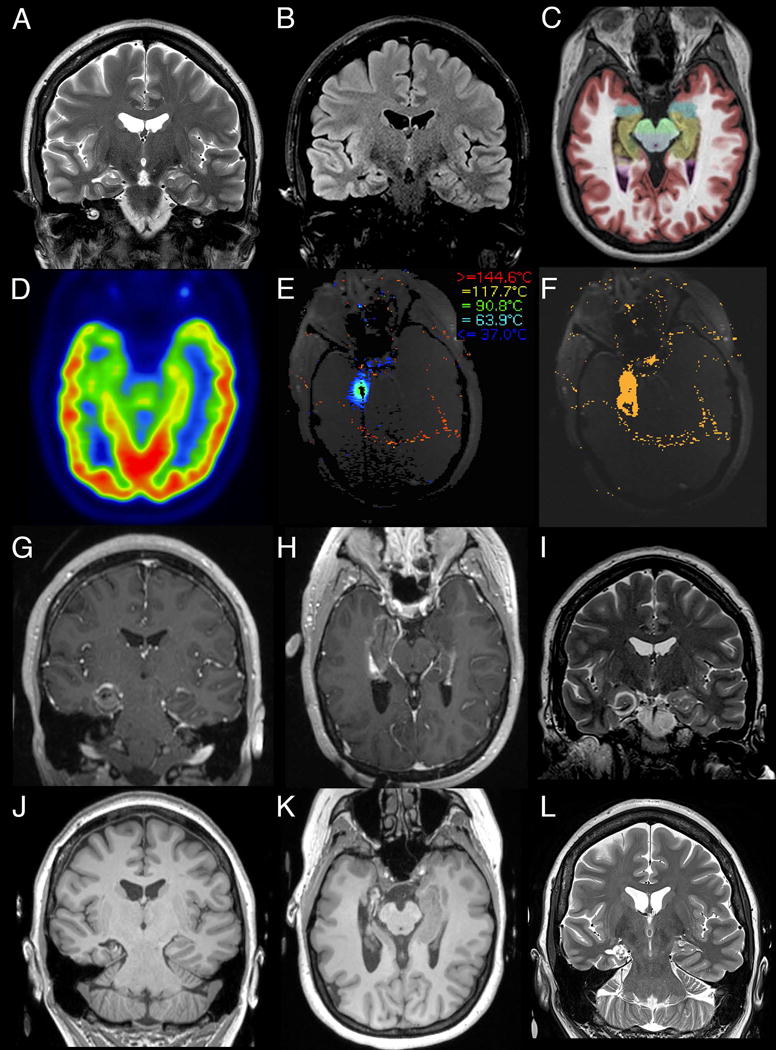

One of two surgeons (REG and JTW) performed SLAH with patients under general anesthesia using the Visualase® system (Medtronic Inc., Lewiston, CO) for laser energy delivery and magnetic resonance thermal imaging, as previously described19–21. Some patients underwent implantation of the laser catheter in the operating room using a standard stereotactic head frame (CRW; Integra Neurosciences, Plainsboro, NJ), but the majority of patients underwent implantation of the catheter in the MRI scanner using a MRI-guided trajectory frame (ClearPoint® ScalpMount SmartFrame, MRI Interventions, Irvine, CA). Trajectories were chosen to penetrate the central portion of the hippocampus from the body at the level of the tectal plate through the head, continuing through the amygdala to the medial temporal pole. The laser fiber was inserted and adjusted if the location was suboptimal. Thermal maps were acquired continuously throughout the laser energy delivery to monitor the target and surrounding tissue temperatures. A 15 W 980 nm wavelength diode laser was used to generate the laser light, first as a low-power sub-ablative test pulse to verify position of the heating, and then at ablative intensities. Multiple pulses were generated along the surgical tract to create a contiguous overlapping ablation zone via manual translation of the fiber within the catheter until the entire target was lesioned. A second tract was employed when anatomically necessary in a minority of cases. After post-ablation imaging with various sequences including gadolinium-enhanced T1, the probe was removed. Patients were typically monitored overnight in a standard hospital room, except for a few patients early in the series who were monitored in the intensive care unit for 1 day, and most patients were discharged on postoperative day 1. Figure 1 presents a series of images outlining the course of the procedure for a representative patient, including preoperative work-up, intraoperative thermal imaging, immediate post-operative imaging and one-year follow-up imaging.

Figure 1. Representative MR images from the pre- and post-operative course of a representative SLAH patient with right MTS.

Pre-ablative diagnostic workup demonstrates the characteristic findings of MTS being hippocampal atrophy with increased T2 (A, coronal) and T2-FLAIR (B, coronal) intensity. This is further highlighted by NeuroQuant (CorTechs Laboratory, San Diego, CA) segmentation (C, axial) with the colorized medial temporal lobe structures (hippocampus in brown and amygdala in blue) overlaid on T1 imaging. Pre-operative FDG-PET (D, axial) demonstrates hypometabolism in the right medial temporal structures, consistent with right MTS. Intraoperative MR thermometry is utilized to guide the procedure (E, axial screenshot of Visualase thermal map generated during LITT of the amygdala) and assess the thermal damage following the procedure (F, axial screenshot of Visualase irreversible damage estimation). Immediate post-ablative imaging demonstrates T1 hypointensity of the ablation target with peripheral contrast enhancement (G, coronal and H, axial, MPRAGE) and T2 (I, coronal) hypointense rings surrounding the ablation. 12-month follow-up imaging demonstrates necrosis and volume reduction of the target tissue with the resulting cavitation on T1 (J, coronal and K, axial MPRAGE) and T2 hyperintensity (L, coronal).